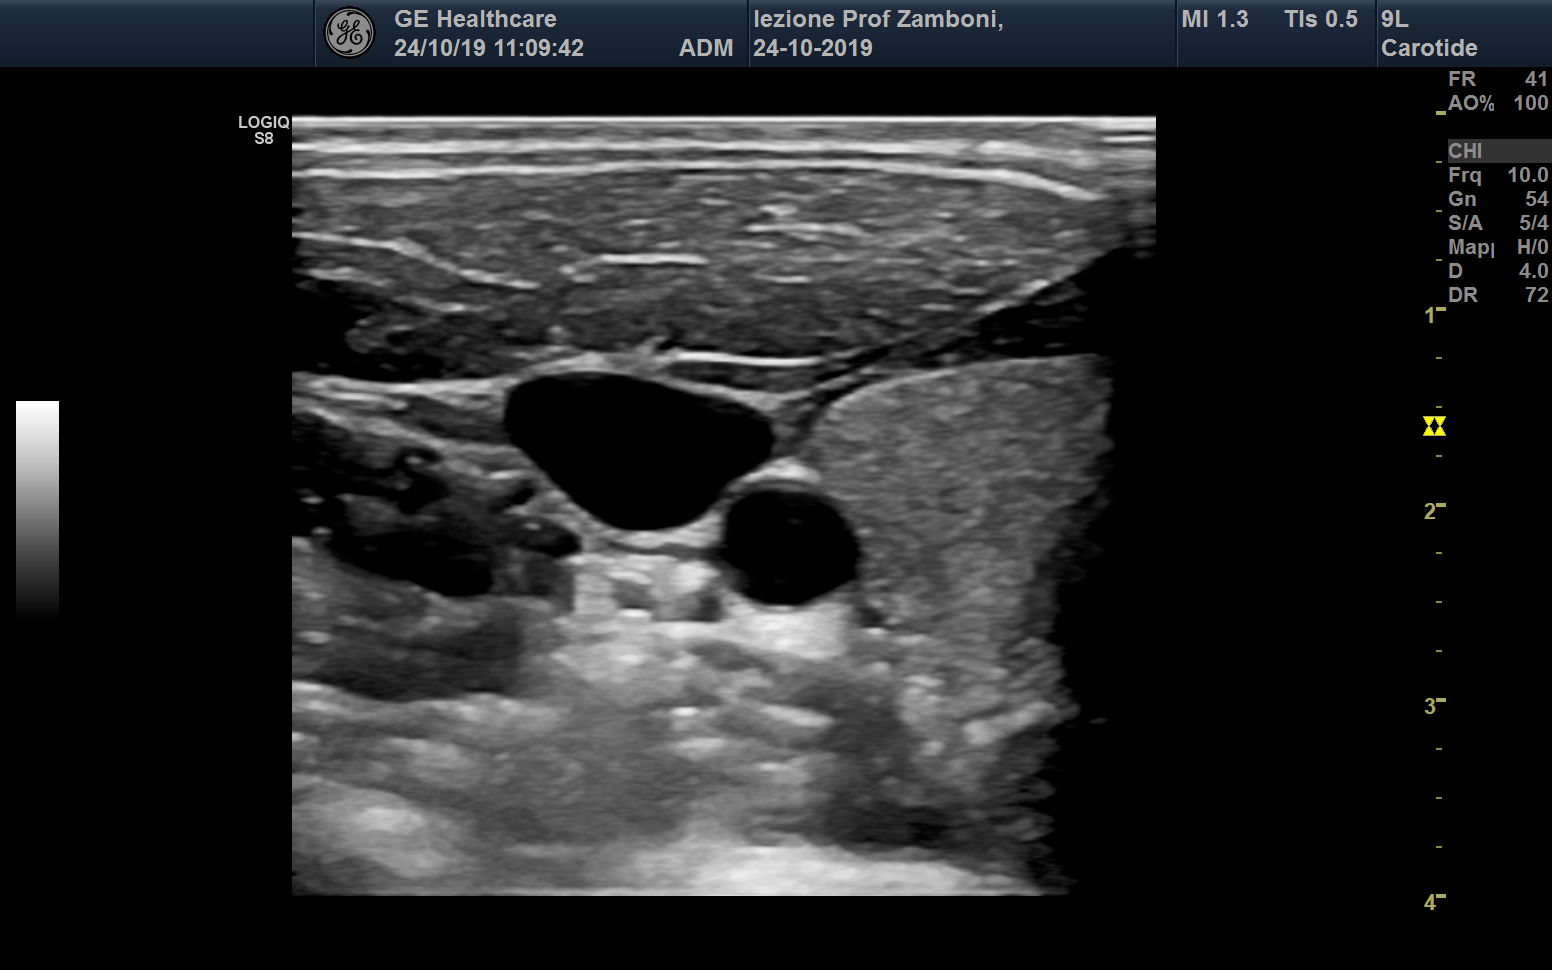

B mode A. Carotide comune V. Giugulare interna Tiroide

B mode A. Carotide comune V. Giugulare interna Tiroide.jpg